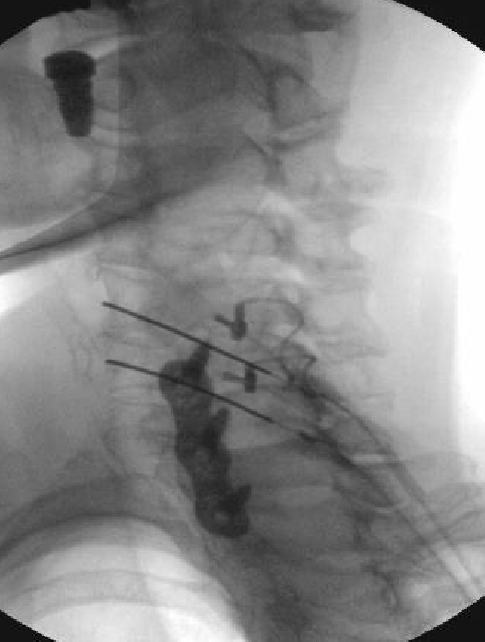

I'm now of the opinion that you will get neuritis if you properly ablate the neck. If you're not getting it, you didn't properly ablate that patient. This is just another case I've decided to post. This happens with nearly every patient I do...

Critique my technique guys. Is there something I'm not doing? I've tried burning 90-120 sec. Increasing the temp, lowering the temp.

Technique looks fine, the bottom one could be a touch closer to os. I’m the higher you go the more common. I do 90 seconds same gauge needle and don’t get it as commonly with same technique. I do tell them about it in clinic then again in preop and it’s self limiting. I had significant post op neuritis and went back 2 months later and did an MBB and it went away in one, other sent for surgery. Pt noted previous to her previous surgery she had a similar feeling and went for surgery and went away, so potential confounded. Of note I don’t put steroid and use marcaine, I wonder if using different local has any effect

I’d like to know how you define neuritis? Most of don’t get it as much and your technique looks fine.

For me neuritis is sharply increased pain after RFA including a sunburn type feeling, that lasts for over a month. Neuritis at TON, will also include a significant headache in the days or weeks after the RFA.

Not just significant soreness for 2-3 weeks plus or minus a little paresthesia for same time period in the skin overlying the lesion.

That is just normal cervical RFA post procedural pain.

Why are you doing RFA at a fused level?

i believe medicare will not cover RFA of a fused level.

i saw that too, but when you look at the AP images...